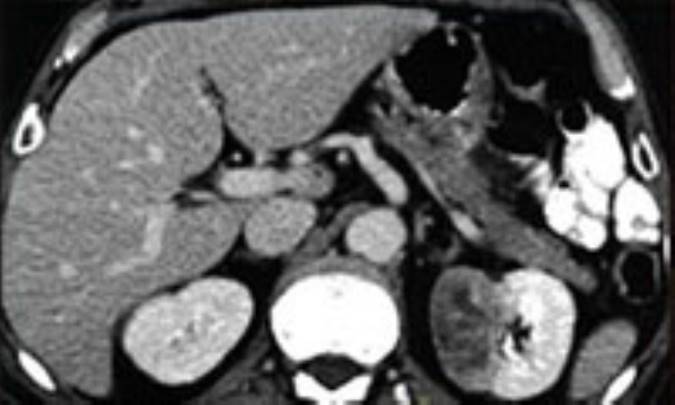

آزمايشات‌ تشخيصي‌ ممكن‌ است‌ عبارت‌ باشند از آزمايش‌ خون‌ و ادرار براي‌ ارزيابي‌ كار كليه‌ و براي‌ تشخيص‌ وجود خون‌ در ادرار. همچنين‌ ممكن‌ است‌ توصيه‌ به‌ انجام‌ سي‌تي‌ اسكن‌، سونوگرافي‌، آم‌.آر.آي‌، و نوگرافي‌ شود.